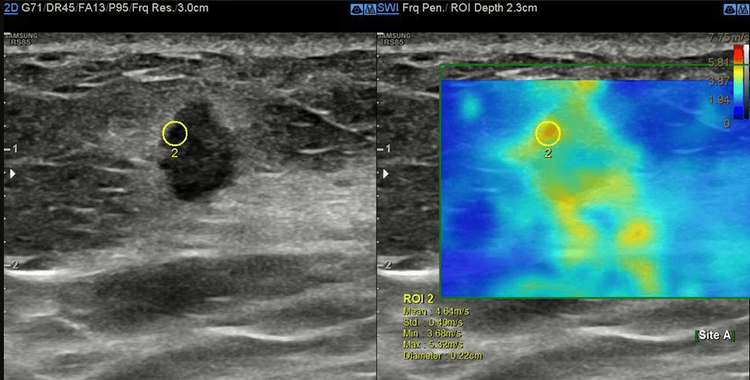

Trong bệnh lý tuyến vú, siêu âm tuyến vú bằng phương pháp đàn hồi mô có tác dụng hỗ trợ phân biệt khối u lành tính và ác tính, giúp hạn chế việc sinh thiết không cần thiết.

Siêu âm đàn hồi mô là kỹ thuật siêu âm giúp cho bác sĩ đánh giá được độ cứng của mô thông qua mức độ đàn hồi của mô khi chịu một tác động của lực cơ học. Các mô bệnh lý có thể cùng độ hồi âm, nhưng sẽ có độ cứng khác nhau, các mô càng ác tính thì độ cứng sẽ càng tăng lên. Chính vì thế, khi đánh giá được độ cứng của mô tổn thương sẽ cung cấp thêm thông tin về bản chất của mô đó.

Phương pháp siêu âm đàn hồi mô bằng cách tác động một lực từ bên ngoài lên tổn thương để gây ra biến dạng tổn thương như trên được gọi là tạo hình đàn hồi bán tĩnh hay còn gọi là đàn hồi gây biến hình. Khi thực hiện kỹ thuật, người làm siêu âm ấn đầu dò bằng một lực nhất định để tác động lên mô tổn thương.

Trong bệnh lý tuyến vú, siêu âm tuyến vú bằng phương pháp đàn hồi mô có tác dụng hỗ trợ phân biệt khối u lành tính và ác tính, giúp cho việc hạn chế sinh thiết không cần thiết.

● Bước 4: Kỹ thuật thực hiện trong khoảng 5 đến 10 phút. Đầu dò siêu âm sẽ thu nhận và mã hóa ra sóng bằng màu sắc giúp bác sĩ lượng hóa được độ cứng của mô.